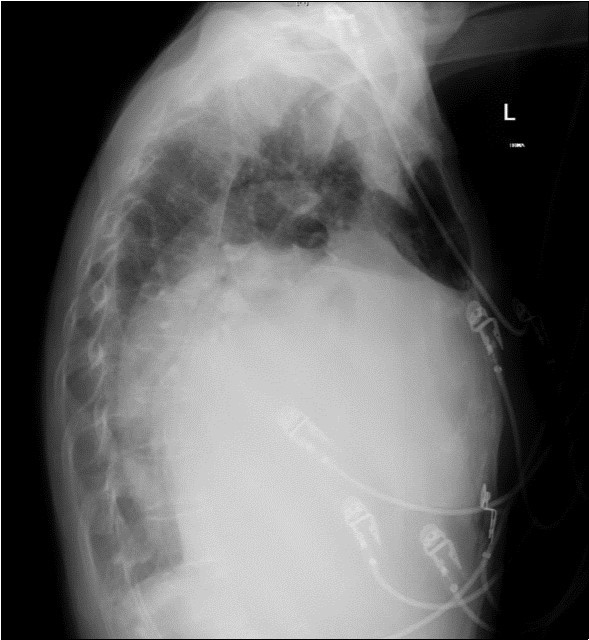

A 64-year-old woman was admitted to the Intensive Care Unit (ICU) after a medical emergency team (MET) call from the cardiology ward due to a reduced level of consciousness and respiratory distress. Past medical history included rheumatic fever as a child and chronic atrial fibrillation. She had been admitted to hospital 3 days previously with worsening shortness of breath. On observation she was drowsy but rousable to voice, with a respiratory rate of thirty breaths per minute. Examination revealed a raised jugular venous pressure, a pan-systolic murmur as well as a long mid-diastolic murmur, both loudest at the apex and radiating to the axilla, a soft first heart sound, a displaced tapping apex beat, and bi-basal medium-intensity inspiratory crepitations. Her electrocardiogram showed atrial fibrillation with a rapid ventricular response of 126 beats per minute. Her arterial blood gas demonstrated an acute on chronic respiratory acidosis with a pH 7.02, PaCO2 176 mmHg, and a HCO3- of 43 mmol/L. An antero-posterior (AP) chest x-ray on admission displayed cardiomegaly, splayed carina and hilar venous congestion, with a lateral film showing the left atrium occupying a significant part of the chest cavity (see Figure 1a, Figure 1b).

Figure 1b.Chest X-ray Lateral view. Findings showing enlarged left atrium occupying large amounts of the thoracic cavity, both horizontally and vertically